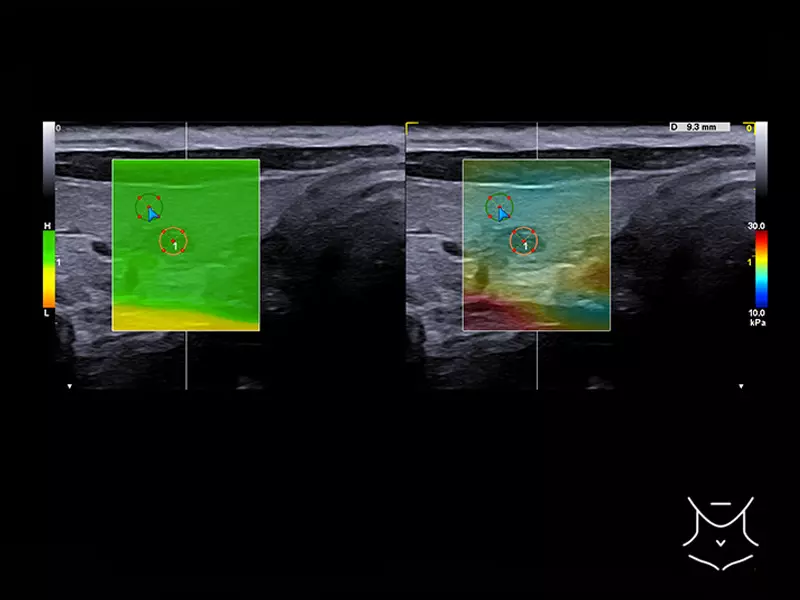

MyLab™9 Platform - Dual ElaXto characterization on breast lesion

MyLab™9 Platform - Dual ElaXto characterization on breast lesion